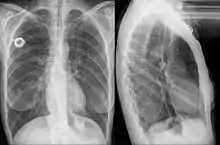

Esophageal stent

An esophageal stent is a stent (tube) placed in the esophagus to keep a blocked area open so the patient can swallow soft food and liquids. They are effective in the treatment of conditions causing intrinsic esophageal obstruction or external esophageal compression. For the palliative treatment of esophageal cancer most esophageal stents are self-expandable metallic stents. For benign esophageal disease such as refractory esophageal strictures, plastic stents are available. Common complications include chest pain, overgrowth of tissue around the stent and stent migration.